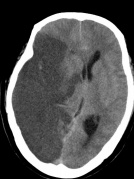

CT检查又贵还有辐射,重复检查是不是就是浪费钱还过度检查了?其实一些情况下,重复检查很有必要。比如对于缺血性脑梗死的患者,早期在颅脑CT上可能没有异常,大约24小时后才能见到因缺血而造成的低密度脑梗死灶。碰到这种情况,要结合病史、病人现况,在24小时后或者更长时间以后给予CT复查,确认诊断。比如,下图中,左图为患者左侧肢体乏力4小时后的颅脑CT图像,右图为患者两天后的颅脑CT图像。发病4小时后的颅脑CT图未见明显异常,而2天后可见大面积的低密度脑梗死灶。

发病2天后的颅脑CT图